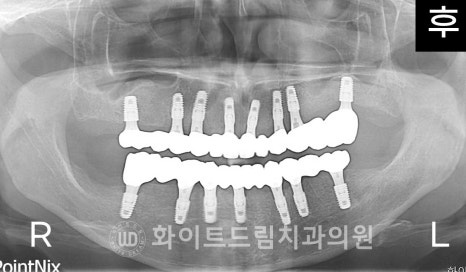

X-RAY 사진을 보면

전체적으로 잇몸뼈가 많이 녹아내려있고,

치아가 없는 오른쪽 상악 어금니 부위의 골 흡수가 크게 진행된 것을 보실 수 있습니다.

환자분의 x-ray 사진을 보면

어떤 임플란트는 잇몸뼈 안에 있고,

어떤 임플란트는 잇몸 밖을 노출되고 있음을 확인하실 수 있는데

이 차이가 바로 1차 수술과 2차 수술의 차이점입니다.